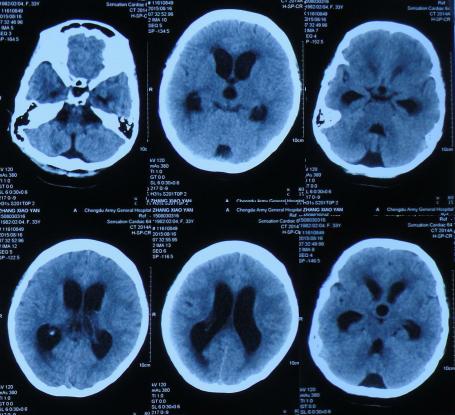

第1家医院治疗16天后即2015年8月19日,间断头痛,腰穿颅内压仍高,查头部CT示脑室进一步扩张(图-5)。

图-5:2015年8月19日头部CT